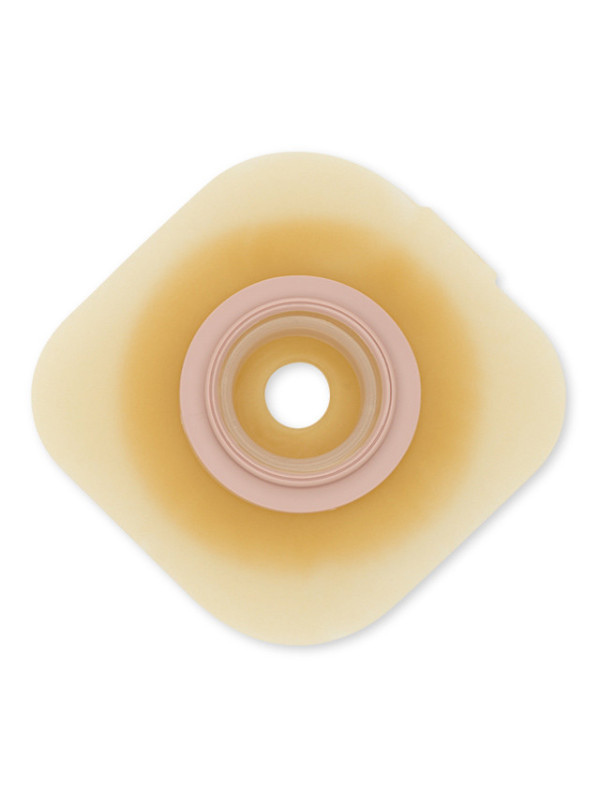

Płytka stomijna Nova™ 2 Convex 55 mm to zaawansowane rozwiązanie dla osób z wklęsłą lub trudną do zaopatrzenia stomią. Dzięki wypukłemu profilowi (6 mm) i nowoczesnej barierze hydrokoloidowej GX, zapewnia pewne przyleganie, ochronę delikatnej skóry oraz bezpieczne i szczelne połączenie z workiem stomijnym. System sprzęgania „na klik” gwarantuje prawidłowe zapięcie i komfort noszenia każdego dnia.

Głębokość wypukłości 6 mm – pomaga wypchnąć stomię do wnętrza worka i zapewnia szczelność.

Bariera GX – elastyczna, hydrokoloidowa formuła delikatna dla skóry, zmniejszająca ryzyko podrażnień i maceracji.

Kształt stożkowy – grubszy wokół stomii, cieńszy na krawędziach – dopasowuje się nawet do trudnych obszarów.

Technologia kontroli pH – utrzymuje lekko kwaśne środowisko, wspierając zdrowie skóry.

System sprzęgania z wyraźnym „kliknięciem” – sygnał prawidłowego połączenia płytki z workiem stomijnym.

Kolorowe pierścienie – dla łatwego i wizualnego potwierdzenia bezpieczeństwa zapięcia.

Elastyczne połączenie półstałe – pozwala pierścieniowi dostosować się do ruchów ciała i zmiany pozycji.

Duża powierzchnia klejąca – w formie kwadratowej płytki, dla lepszej stabilności.